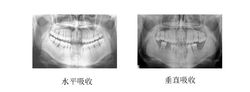

(一)水平型吸收 水平型吸收(horizontal resorption)是最常見的吸收方式.牙槽間隔,唇頰側或舌側的嵴頂邊緣呈水平吸收,而使牙槽嵴高度降低,通常形成骨上袋.

(二)垂直型吸收 垂直型吸收(vertical resorption)也稱角形吸收(angular resorption),指牙槽骨發生垂直方向或斜行的吸收,與牙根面之間形成一定角度的骨缺損,牙槽嵴的高度降低不多(除非伴有水平吸收),而牙根周圍的骨吸收較多.多形成骨下袋.